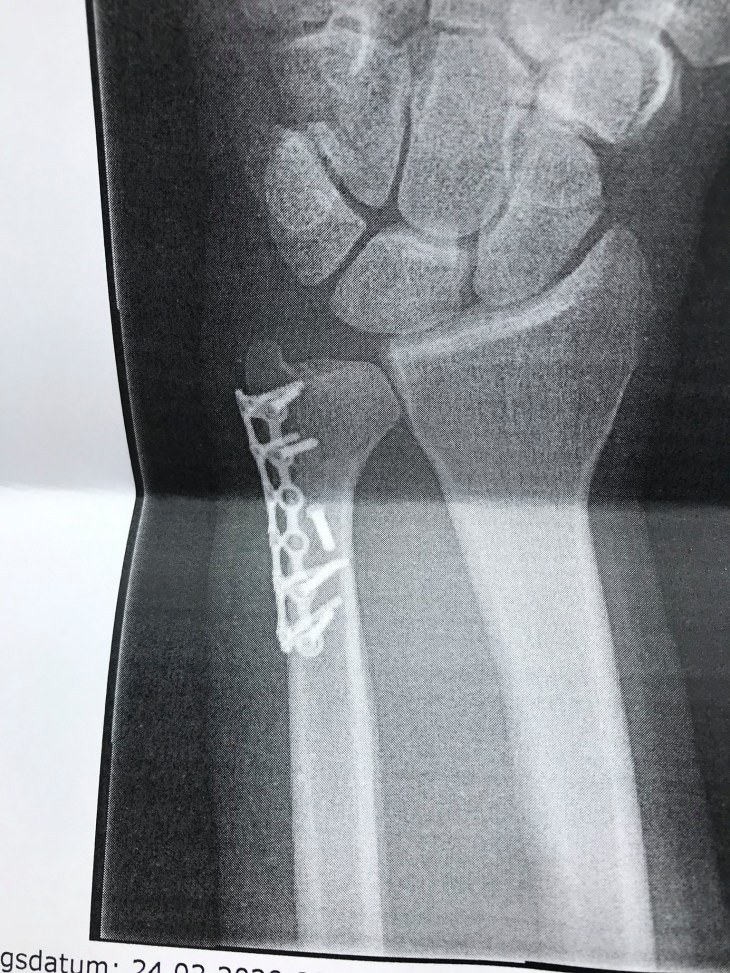

The day was pretty standard. I suck at the Tellerlifts (T or J-Bars) as a snowboarder so I got yelled at a few times in French for being such an idiot on them. Les Houches actually has an awesome side of the mountain with plenty of trees to speed through and rocks to jump off; however, as you can see from the title image, this section proved to be my undoing. I think the slope area is pretty ideal for kids considering the learner’s area and the general ease of the pistes.

I’ll emphasize that this was my FIRST day of a six day trip. After pushing past my hangover by drinking beer (above photo), we spent most of our time on the tree covered side of the mountain and had a pretty awesome time weaving through the greenery. Things went on like this until I stuck my hand out a little too far to make a tight turn and felt a unique new pain as I tried shaking hands with a tree.

This was a pain I had not felt before and I started feeling pretty uneasy. After taking a lift back up and getting to a hut for a beer, I immediately fell asleep in a wooden lounger for over an hour. I didn’t know it, but this was my body’s way of saying, “Power down you idiot. You broke something.”

Since I wasn’t about to wimp out and quit on my first day of a six day trip, I made a choice (a stupid one) to postpone any visit to the Doctor until this trip was over. However, this day was over, for me. As we made our way down the icy and terrible home stretch down into the village, most of our time was spent swearing at the awful conditions that this Winter had given us.

To really paraphrase Les Houches: I thought it was a cool and uniquely “local” feeling spot overshadowed by bigger places next door. I really enjoyed the tree runs regardless of breaking my arm. Depending on your drive, you may opt for the larger areas in the region; however, I’ll say that the slopes here are pretty friendly for novice-to-intermediate skilled kids (or adults). A quick Google will yield several ski schools for kids that look pretty reasonably priced. If I ended up in the region, I’d probably come back. It would be a little difficult to justify a 5-6 hour drive just for Les Houches; however……I think a snowboarding trip to the Chamonix region is well served with a day-trip to Les Houches.